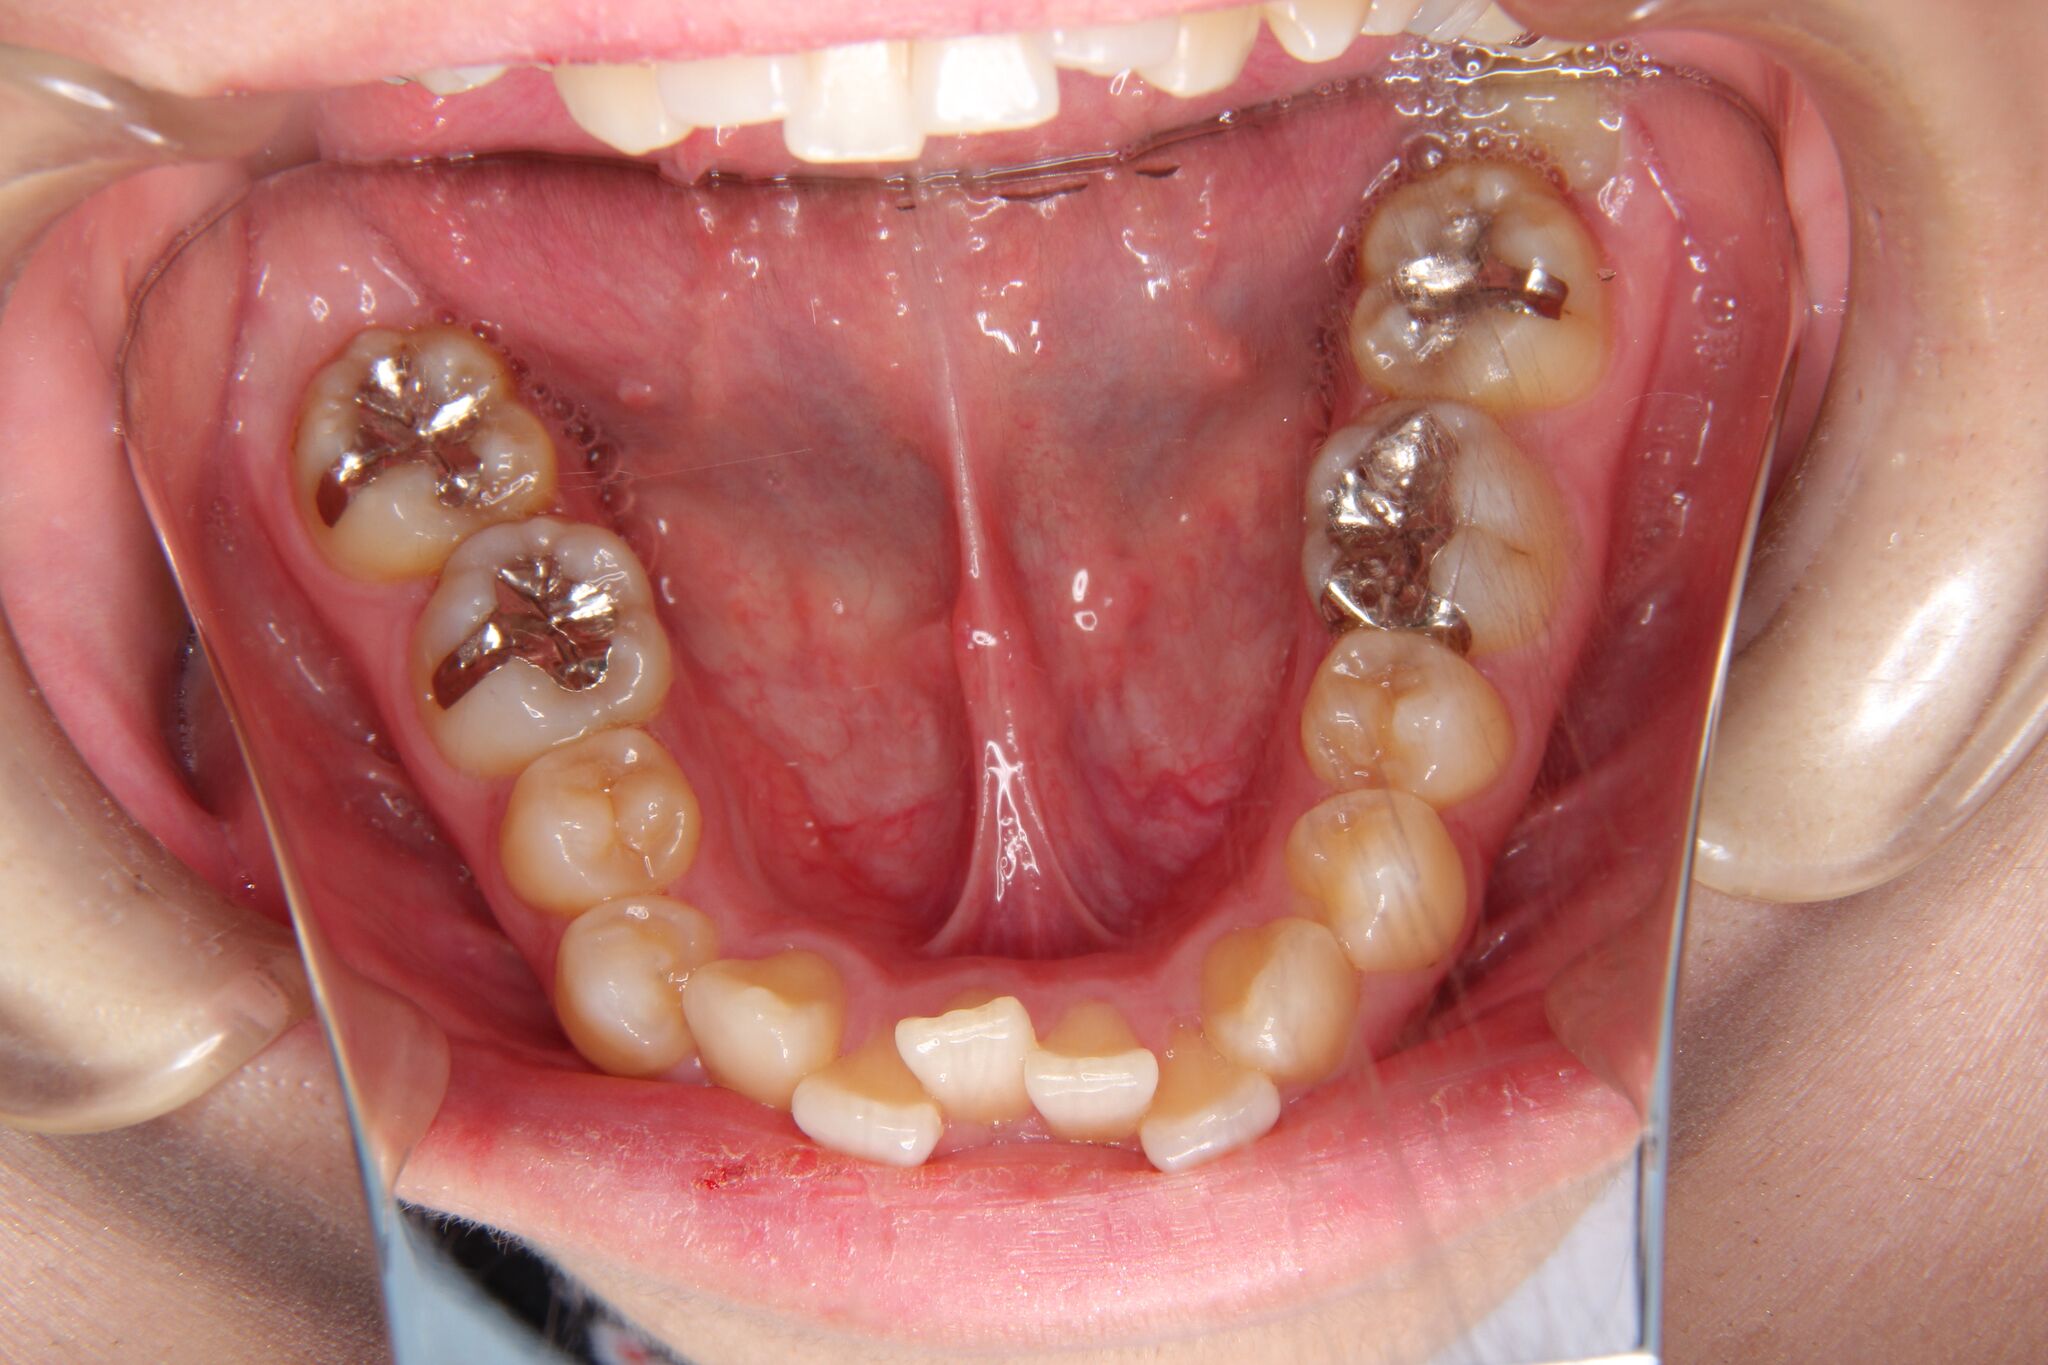

- 治療前 治療後

下の前歯に叢生(凸凹)がかなり認められました。

インビザラインによるマウスピース矯正にて、コントロールしました。

噛み合わせが深い(過蓋咬合)のため、下の前歯が内側に傾斜して、叢生ができている状態でした。このようなケースは、単純に歯の凸凹を改善しただけですと、すぐに装置をはずすと凸凹歯に後戻りしてしまうことが多くあります。

そのため、噛み合わせの高さを挙上しながら、凸凹を改善していく必要があります。